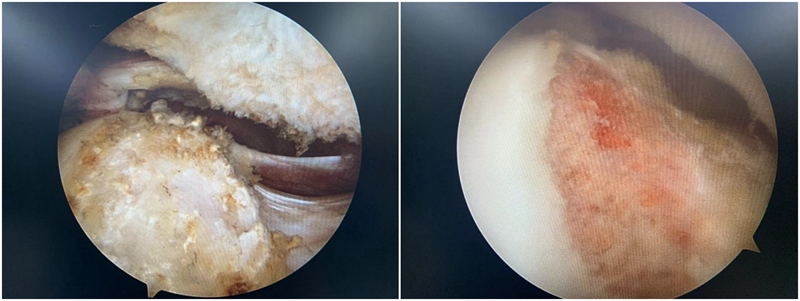

图9 Cam型撞击,通过磨钻磨除

2.盂唇损伤的治疗:盂唇损伤广泛存在于髋关节撞击综合征中。对于存在修复条件的盂唇损伤,目前推荐行盂唇修复术;而对于盂唇严重磨损无法修复或横断的情况,则可考虑行盂唇清理、盂唇部分修复或盂唇重建术。手术原则是对损伤的髋臼盂唇尽量予以缝合修复,恢复髋臼盂唇的解剖结构,从而恢复髋臼盂唇的功能,避免由于髋臼盂唇缺损造成的髋关节退变。

图10 髋关节盂唇损伤及修复

3.软骨损伤的处理:髋关节撞击综合征患者除了常常导致髋关节盂唇的损伤之外,还常常造成髋关节软骨的损伤,而且髋关节软骨损伤的部位也常常发生在髋臼的前方。目前对于任一关节的软骨损伤治疗都是难点,对于髋关节这样的负重关节更是如此。对于怀疑存在软骨损伤患者,则应早期进行手术治疗,尽可能避免髋关节退变的结局。

图11 撞击导致软骨损伤